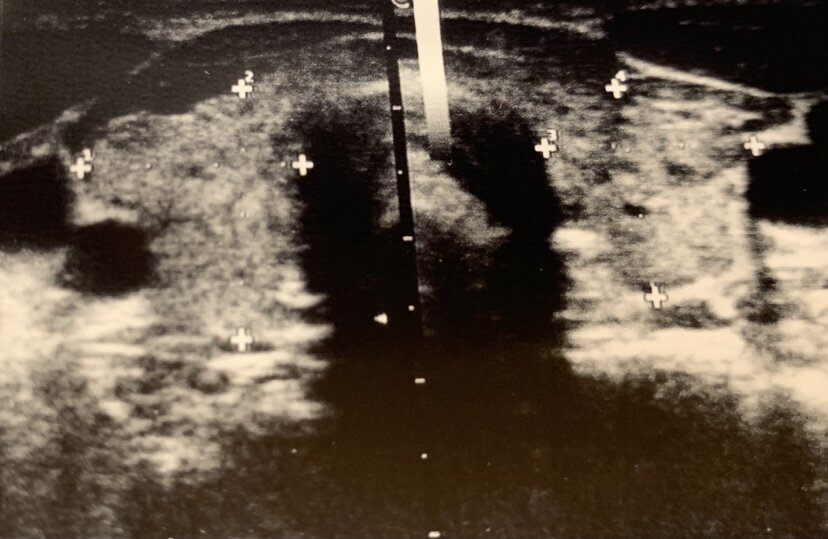

У таких пациентов с тиреоидитом обычно повышается уровень антител к ТПО и ТГ, на УЗИ определяется снижение плотности и диффузная неоднородность.

Выраженность аутоиммунного воспаления может меняться с течением времени, что можно увидеть на УЗИ.